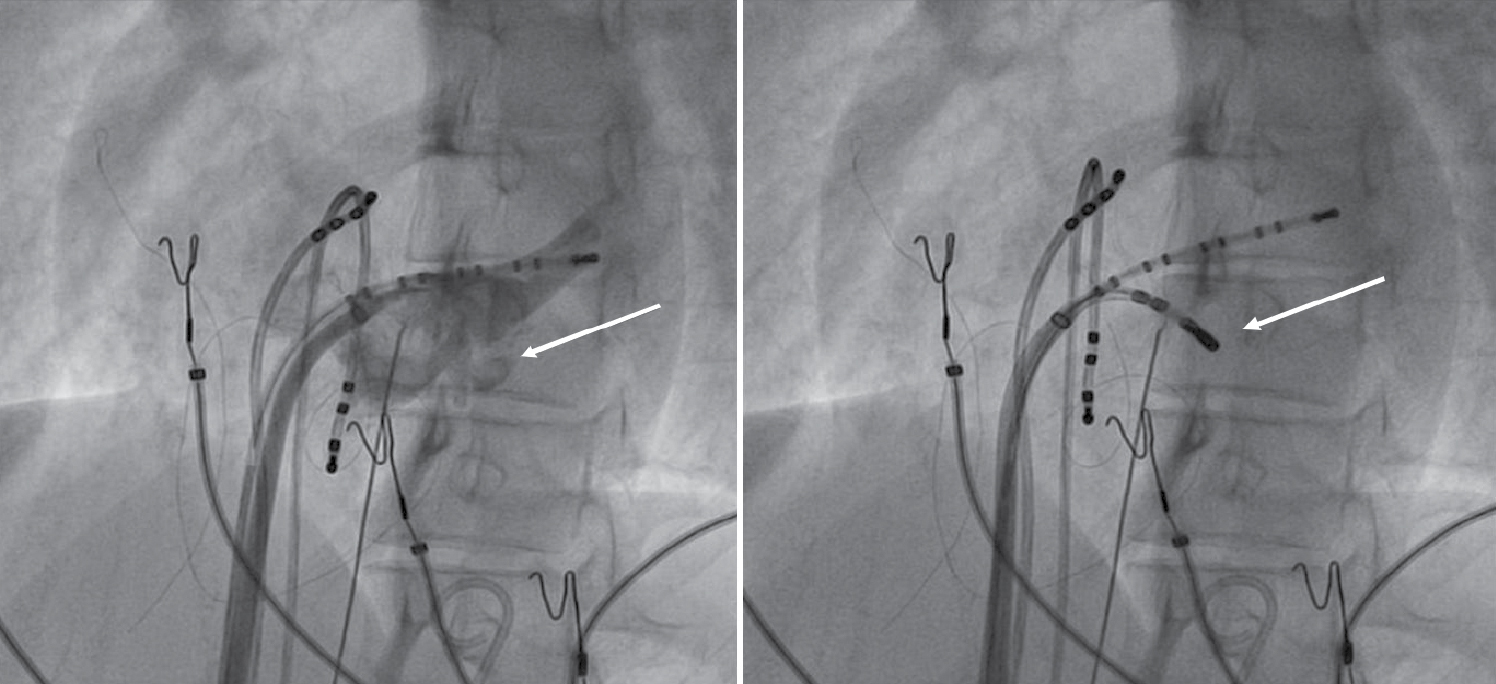

Later on, during programmed atrial stimulation with burst pacing, patient developed another broad complex tachycardia (TCL = 220 ms) with 1:1 AV relationship. The tachycardia was hemodynamically unstable and led to ventricular fibrillation and required direct current cardioversion (DCCV) with 200J (Fig. 4). With the help of steerable ablation catheter, earliest atrial activation during ventricular pacing and earliest ventricular signal in sinus rhythm was mapped at the septal tricuspid annulus (RA mapping) and septal mitral annulus (LA mapping). Afterwards coronary sinus angiogram was taken, which showed a coronary sinus diverticulum near the decapolar coronary sinus 5-6 electrodes (Fig. 5). Radiofrequency applications were delivered at the neck of diverticulum that leads to disappearance of pre-excitation (Fig. 6). Afterwards aggressive programmed stimulation done on and off with isoproterenol that did not induce any atrial arrhythmias.

Figure 5. Coronary sinus angiogram (left) showing coronary sinus diverticulum and site of successful ablation (right).